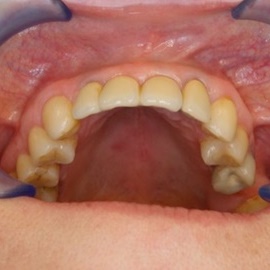

Pacjentka lat 58, prowadzi aktywne życie zawodowe. Odczuwała dyskomfort przy użytkowaniu protezy, dodatkowo przy uśmiechu odsłaniała klamry utrzymujące protezę.

Pacjentka lat 68, prowadzi aktywny tryb życia, dużo podróżuje, przeszkadzały jej klamry widoczne na zębach przy uśmiechu, oraz słaba stabilność protezy, co powodowało dyskomfort przy użytkowaniu.

Pacjentka prowadzi aktywne życie zawodowe, niedawno zakończyła leczenie ortodontyczne, niestety nie nastąpiło po nim właściwe leczenie protetyczne. Użytkowała protezę ruchomą z klamrami dziąsłowymi.